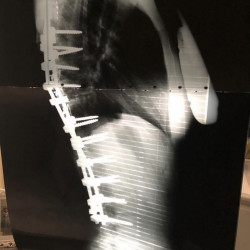

My favorite way to train is by integrating mobility, strength training, and functional fitness to support long-term health and performance. With a fused spine, mobility is essential for recovery, injury prevention, and movement quality. Strength and functional training build resilience, efficiency, and confidence—allowing me to lead by example and show that sustainable fitness is achievable for every body.